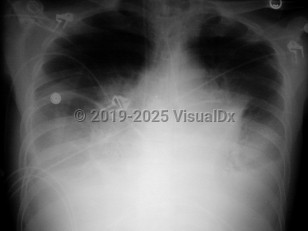

Inclusion criteria can be any one of the following: positive blood cultures, mediastinal adenopathy, or pleural effusions. The patient may also have nonspecific findings such as high fever, dyspnea, confusion, syncope, and nausea / vomiting. If diagnosed in this stage, the prognosis is still good if antibiotics are administered, pleural fluid is drained, and supportive care is provided.

In the past, there were considered to be 2 stages of anthrax: early and late. Based on the clinical, radiologic, and microbiologic findings of the 11 inhalational anthrax victims in 2001, 3 stages have been identified.

Early-prodromal:

The first stage consists of nonspecific symptoms such as fever, dyspnea, cough, headache, vomiting, chills, weakness, abdominal pain, and chest pain. Laboratory tests are also nonspecific at this stage. If diagnosed in the early prodrome stage, the prognosis is very good if the appropriate antibiotics are instituted. These initial symptoms occur for 24-48 hours, and the patient may show signs of transient improvement after 2-4 days.

Intermediate-progressive:

Late-fulminant:

Inclusion criteria can be one of the following: meningitis, respiratory failure (requiring mechanical ventilation), or shock. Findings from the previous stages may be concurrently present. In 2001, no patient who required mechanical ventilation and/or hemodynamic support survived. More recently, a critically ill patient who was exposed unintentionally did survive with critical care support.